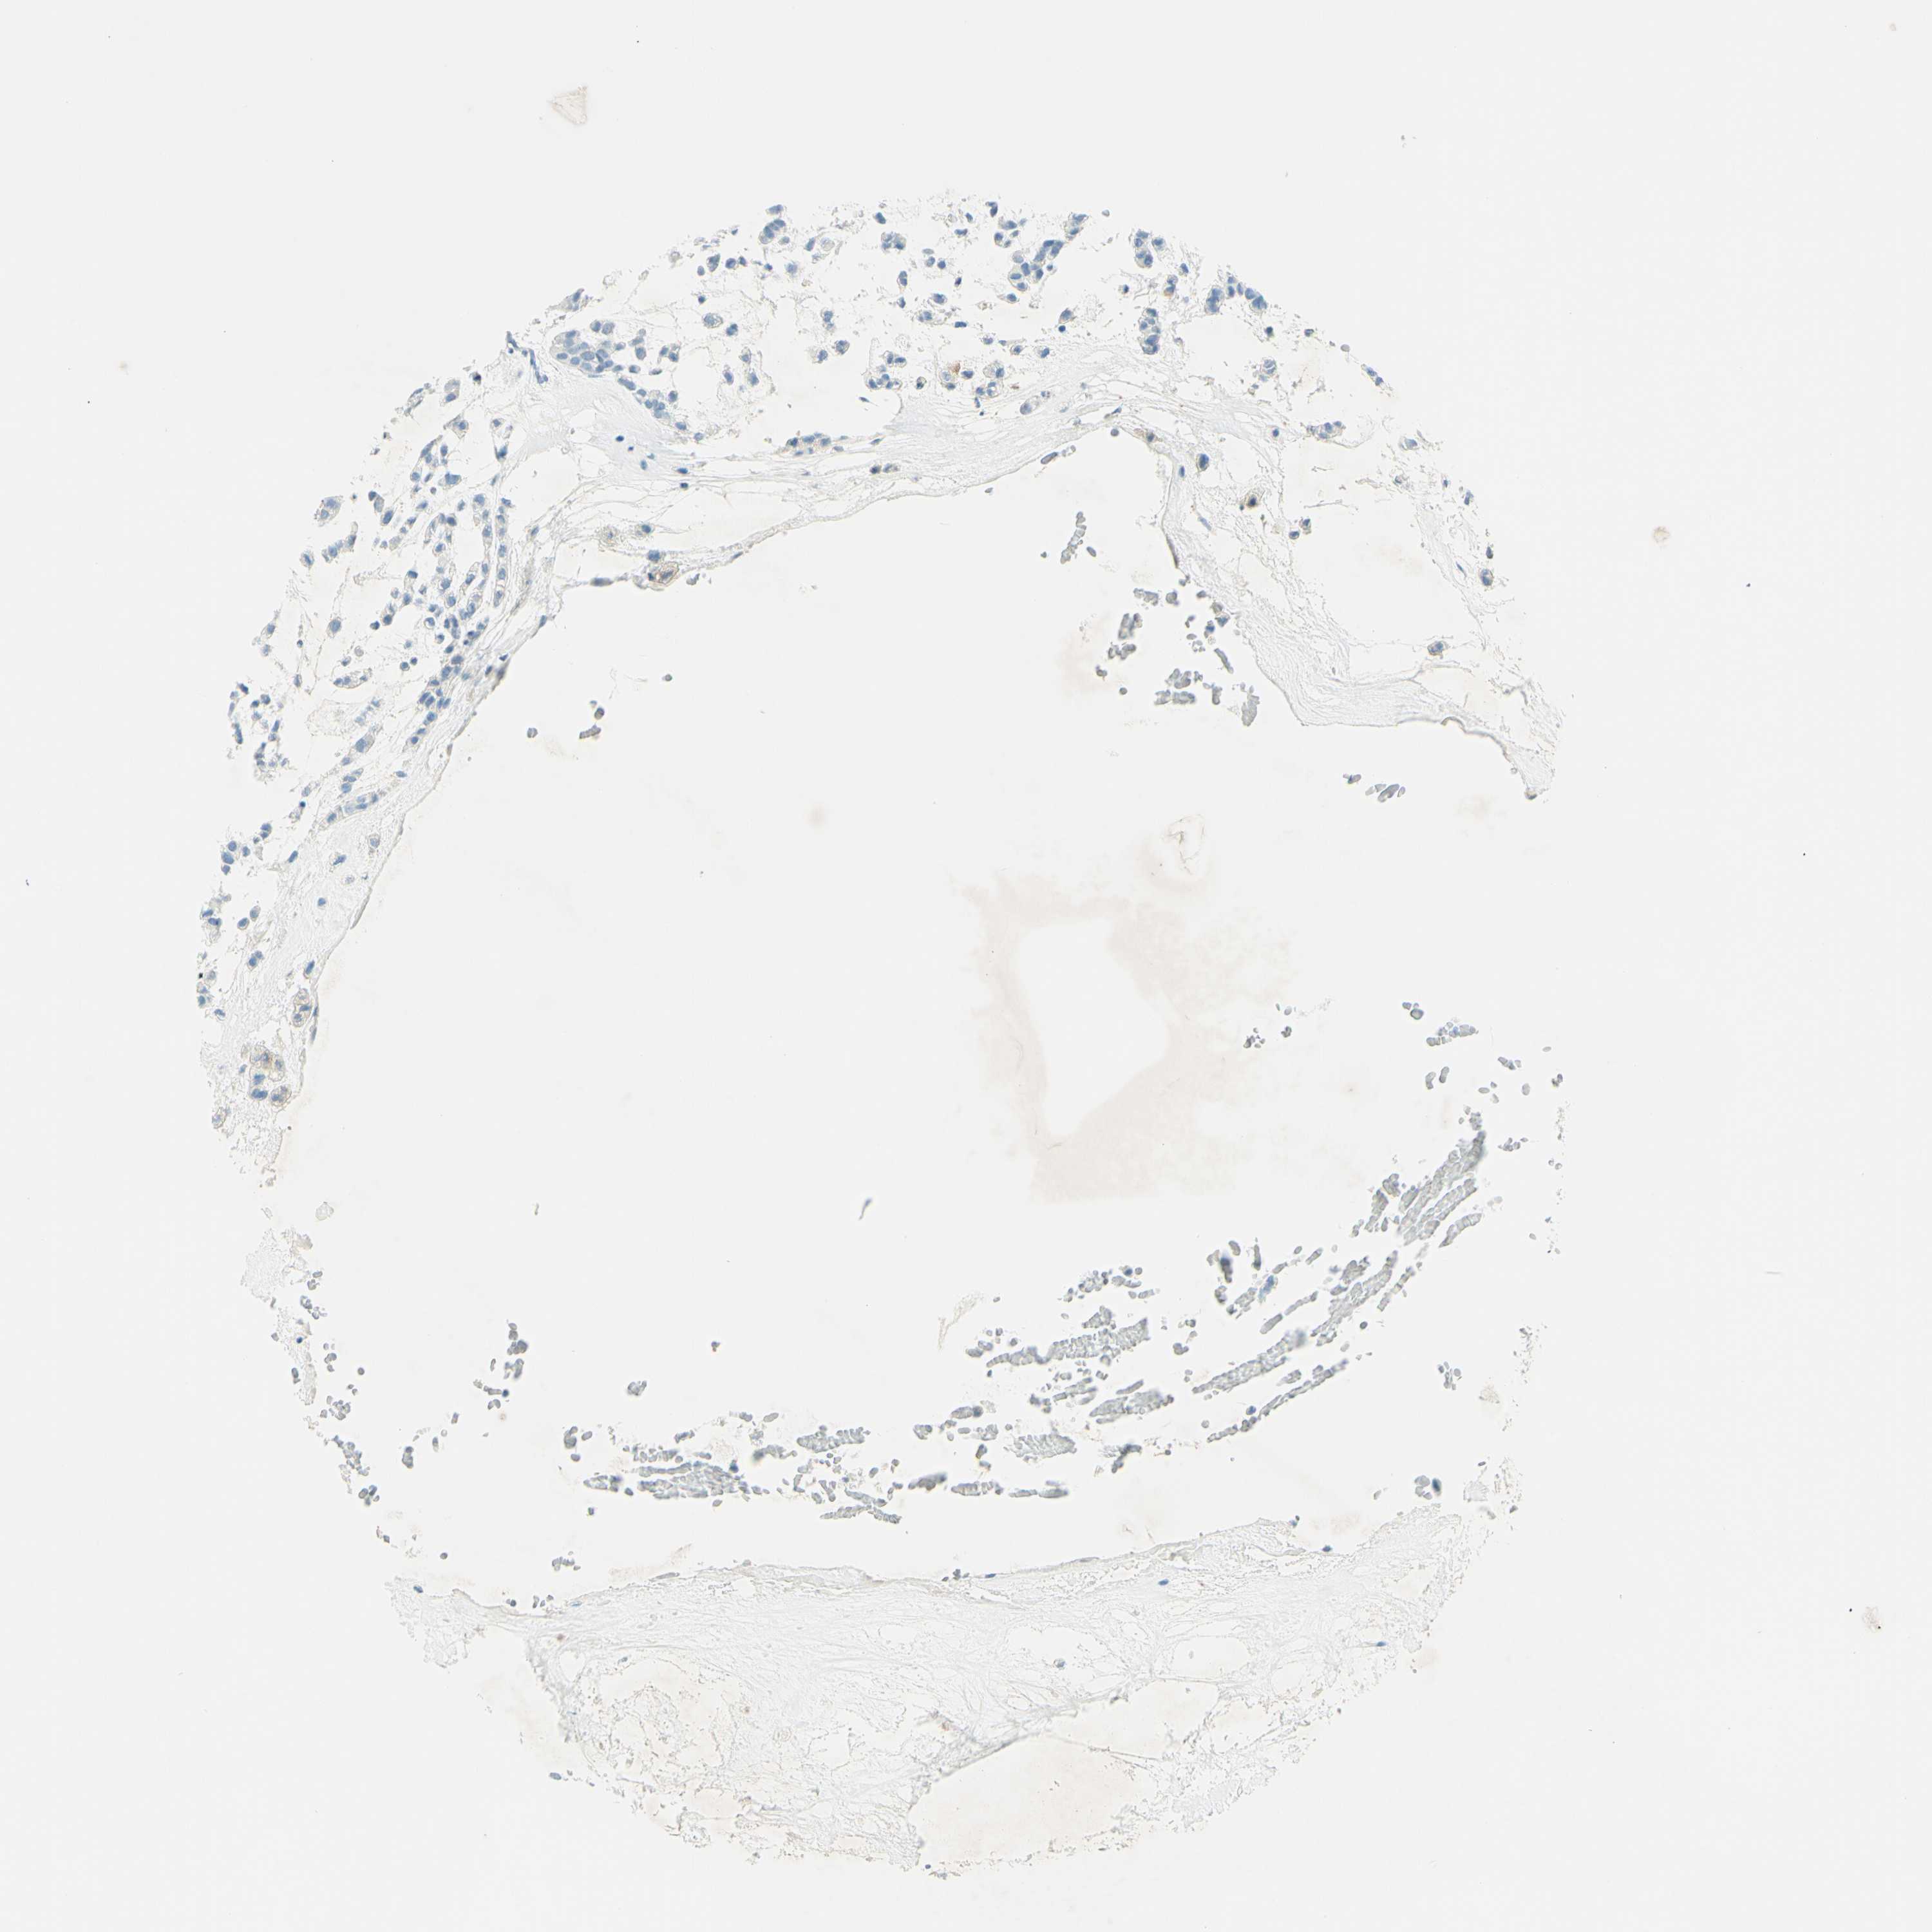

HEAD AND NECK CANCER - Protein expressioni

A mouse-over function shows sample information and annotation data. Click on an image to view it in a full screen mode. Samples can be filtered based on level of antibody staining by selecting one or several of the following categories: high, medium, low and not detected. The assay and annotation is described here.

Note that samples used for immunohistochemistry by the Human Protein Atlas do not correspond to samples in the TCGA dataset.

Antibody stainingi

Antibody staining in the annotated cell types in the current human tissue is reported as not detected, low, medium, or high, based on conventional immunohistochemistry profiling in selected tissues. This score is based on the combination of the staining intensity and fraction of stained cells.

Each image is clickable and will lead to virtual microscopy that enables deeper exploration of all samples and also displays staining intensity scores, fraction scores and subcellular localization as well as patient and tissue information for each sample.

Antibody HPA011284

Antibody CAB026403